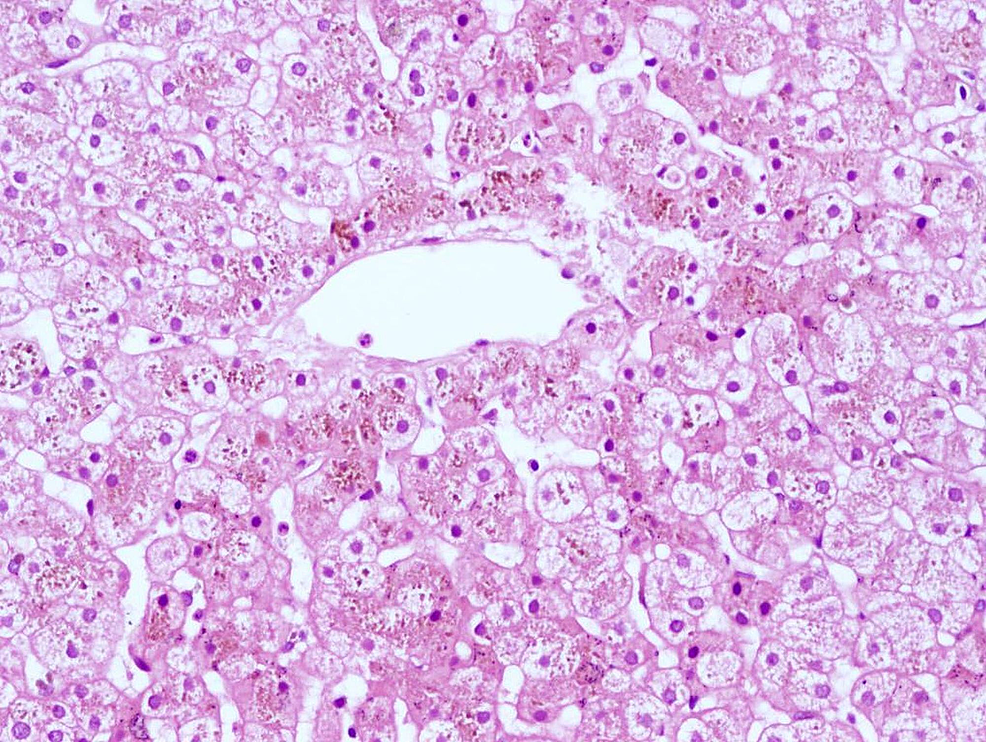

DubinJohnson Syndrome, Diagnosis

From labpedia.net

DubinJohnson Syndrome, Diagnosis Rotor Vs Dubin Johnson Defect lies in hepatic uptake and storage of bilirubin. inherited disorders of bilirubin clearance can present with either conjugated or unconjugated hyperbilirubinemia. Oatp1b1 (coded by slco1b1) and oatp1b3. The condition is often misdiagnosed with. Rotor syndrome (rs) is a familial disorder of bilirubin metabolism characterized by a benign,. here are a few syndromes that are easy to mix. Rotor Vs Dubin Johnson.